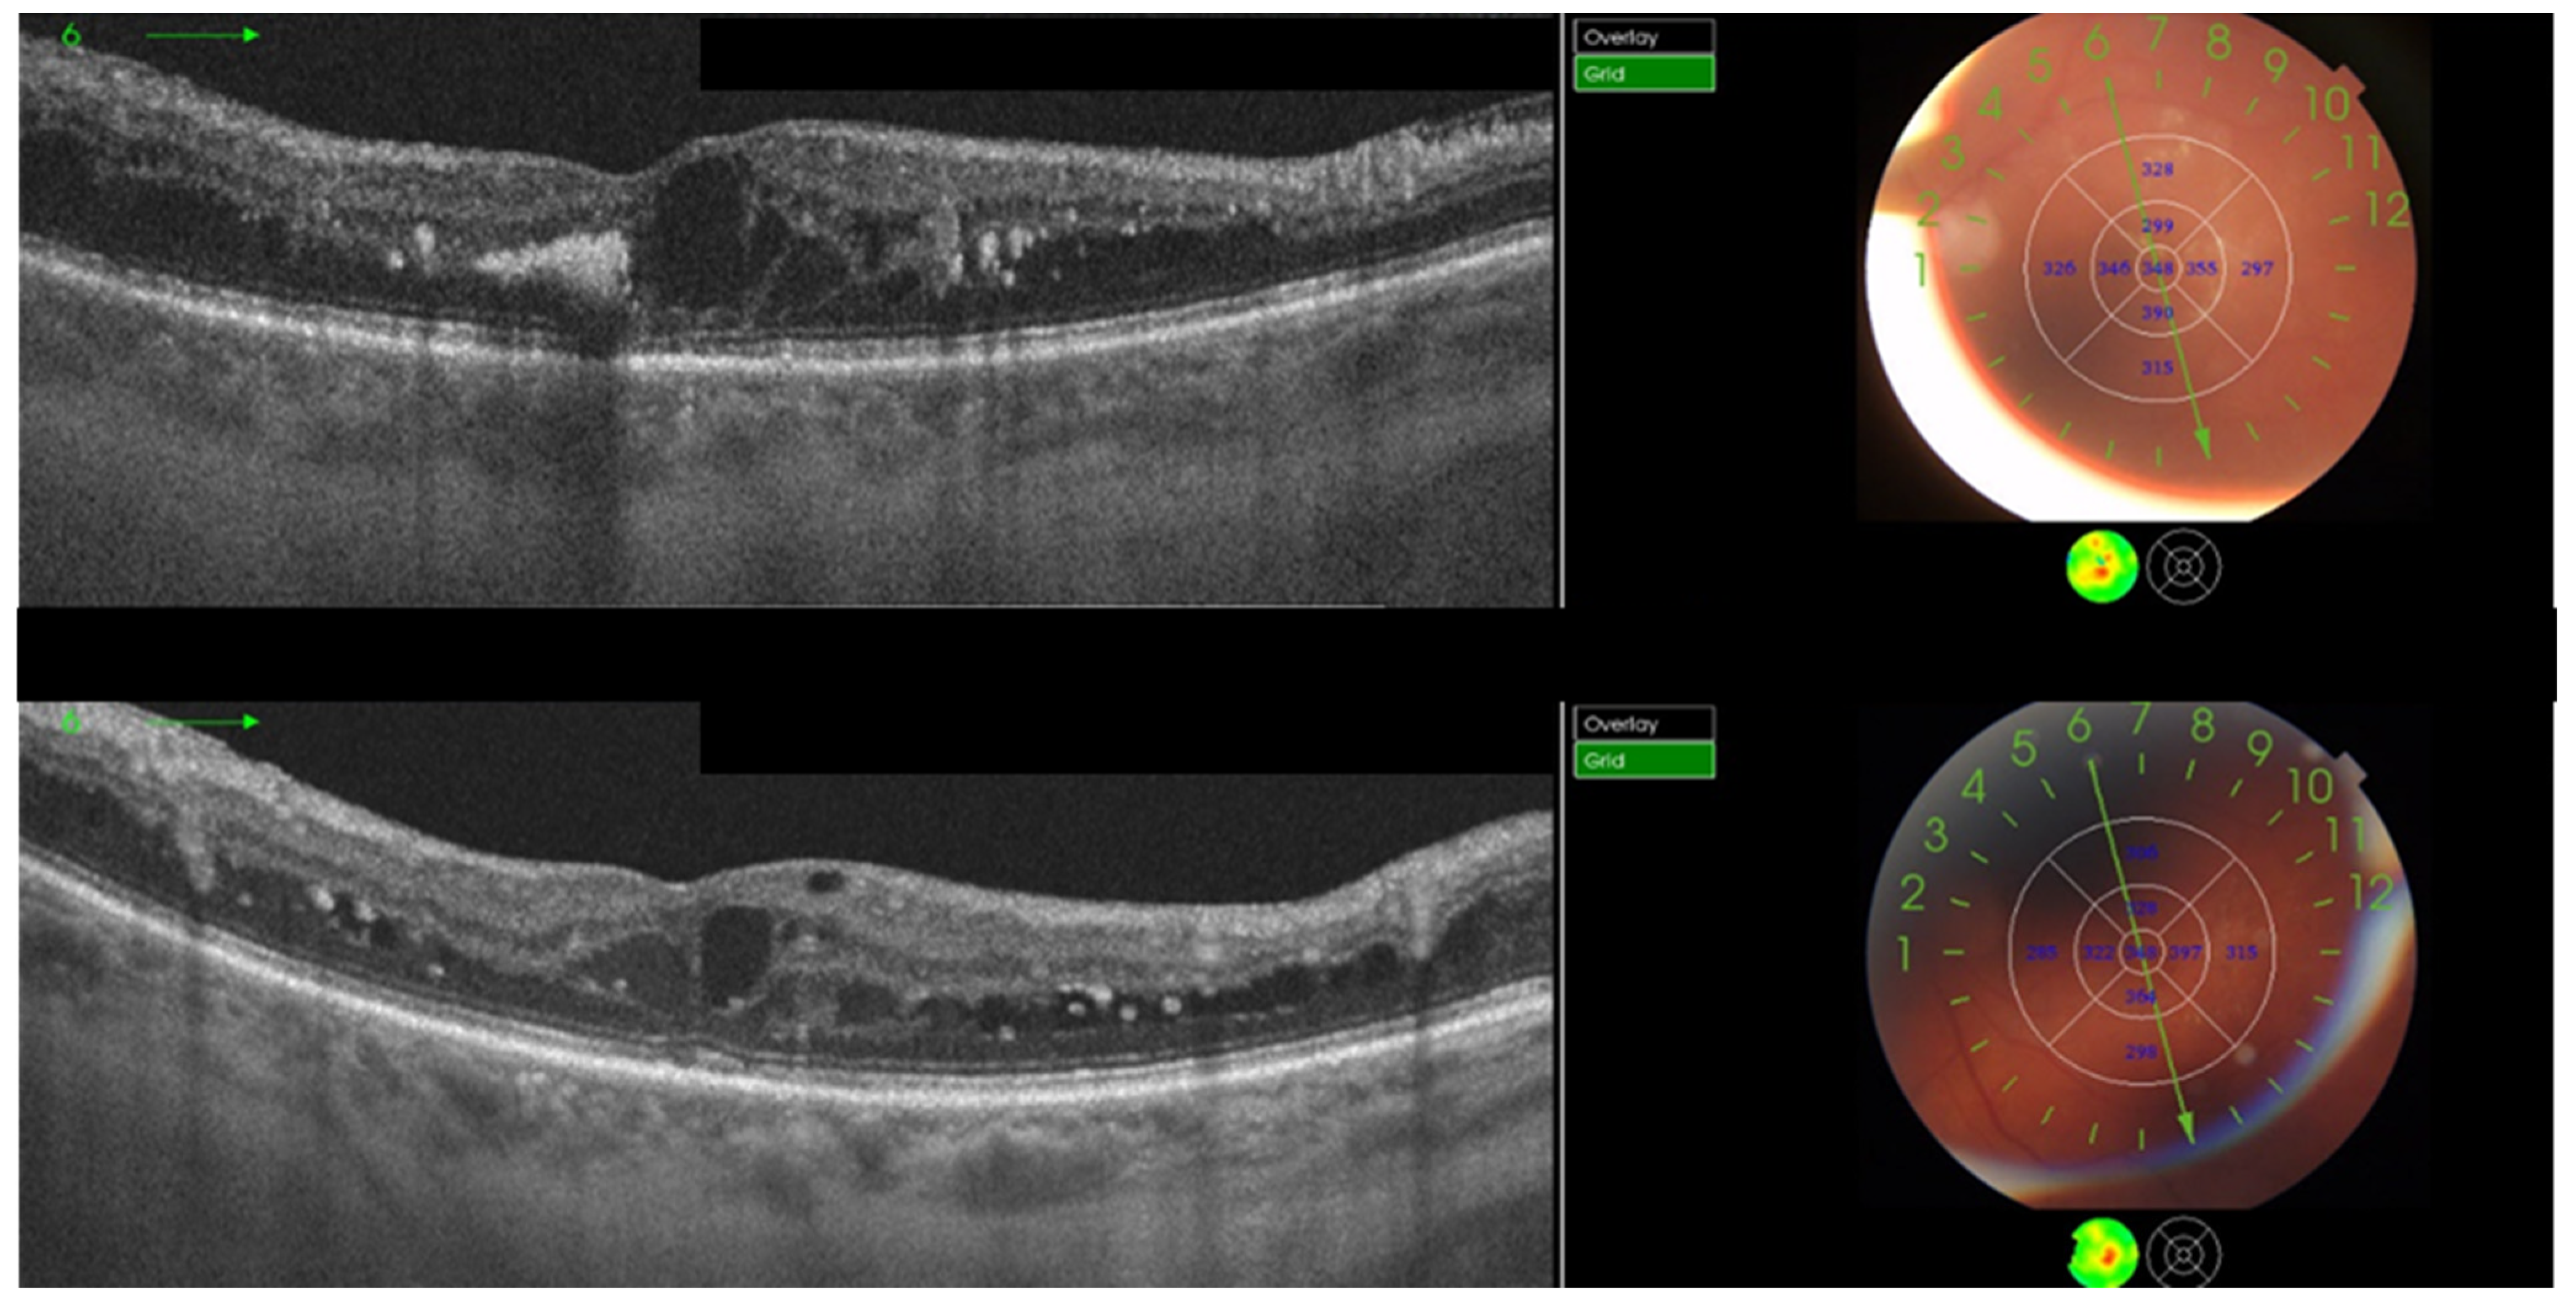

- Hunt, M.; Teper, S.; Wylęgała, A.; Wylęgała, E. Response to 1-Year Fixed-Regimen Bevacizumab Therapy in Treatment-Naïve DME Patients: Assessment by OCT Angiography. J. Diabetes Res. 2022, 2022, 3547461. [Google Scholar] [CrossRef]